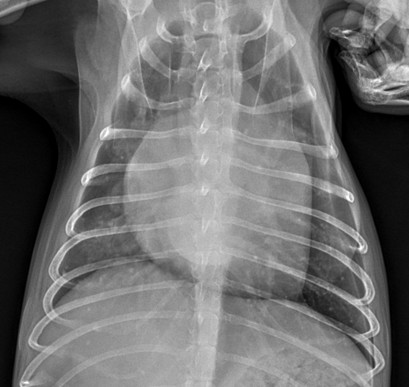

심장 질환 진단에서 가장 중요한 것은 ‘심장의 상태를 얼마나 정확하게 볼 수 있느냐’입니다. 저희 센터는 대학병원급 하이앤드 초음파 장비를 도입하여, 실시간 3D 렌더링으로 정밀 진단이 가능하며, 심장의 구조·혈류·기능을 실시간 고해상도로 관찰합니다.

미세한 판막 움직임, 혈류 속도 변화, 심방·심실 크기와 수축력까지 정밀하게 분석할 수 있어, 심장질환의 조기 발견과 치료 계획 수립에 큰 차이를 만듭니다.